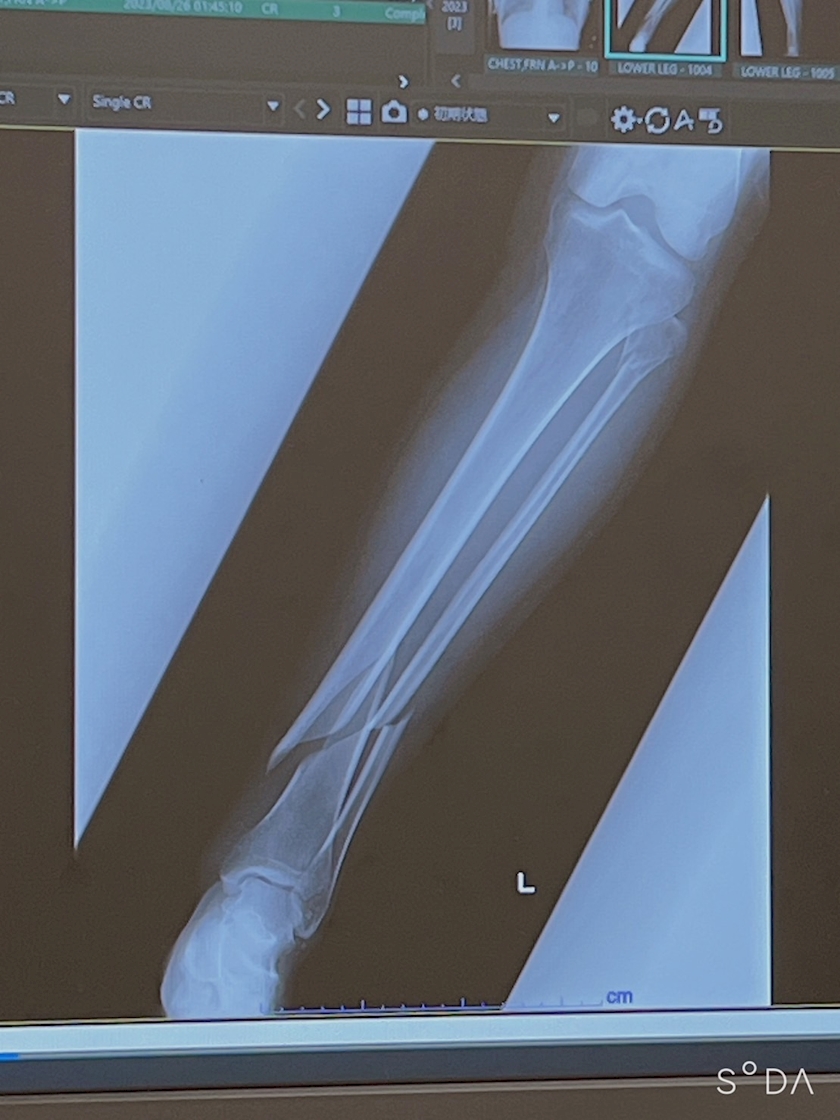

レントゲン撮るけど、、、、

まだ骨くっついてないだろうなぁ😮💨

だって普通に痛いから笑

早く痛みから解放されて普通に歩けるようになりたい😮💨

ばり綺麗に斜め折れ🤪